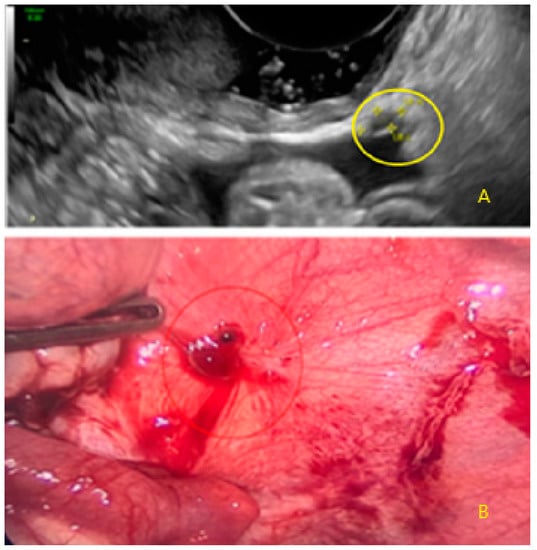

- The lesion may be convex, protruding from the peritoneal surface into the peritoneal cavity (we called this “bulging”), or it may appear as a concave defect in the peritoneum (we called this a “pocket”).

- The presence of velamentous (filmy) adhesions associated to the lesion (we called this a “veil”).

3.1. Cystic Solitary Lesion